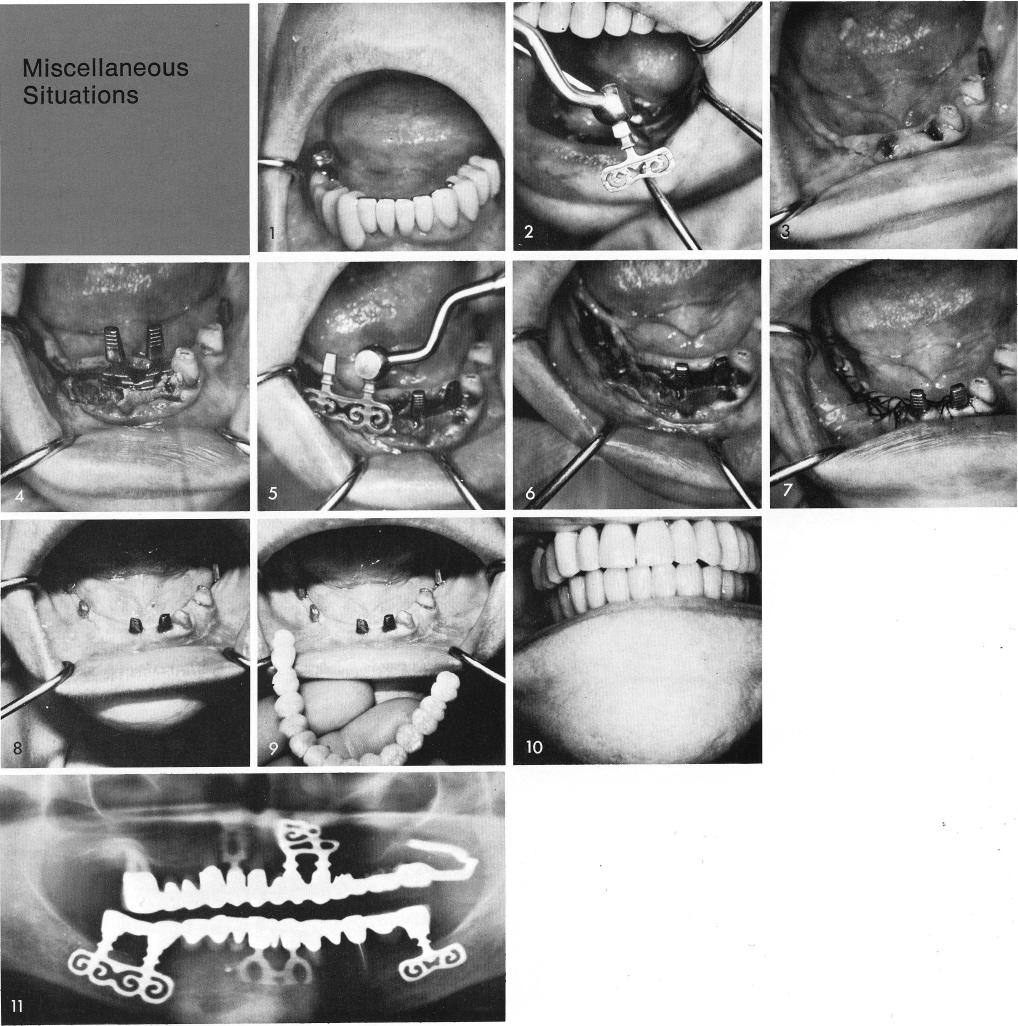

A failing full arch fixed prosthesis required its removal, fig. 1. With only two teeth worth-while to save, bladevents were inserted into pre-determined grooves around the arch, figs. 2, 3, 4, 5, 6, and the tissues were closed with triple 0 silk sutures, fig. 7. The healing was rapid and uneventful, fig. 8. A full arch porcelain-baked-to-metal restoration was cemented into position, figs. 9, 10. A post-operative x-ray, fig. 11.

1 Removal of failing full arch mandibular fixed prosthesis